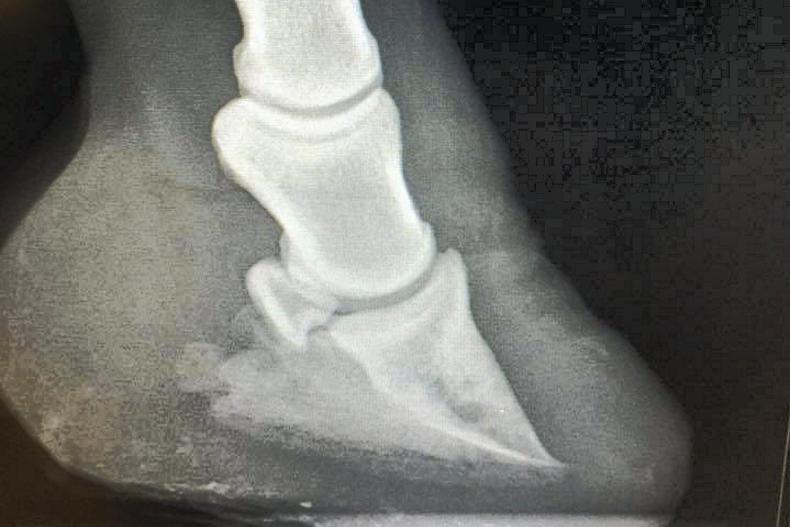

The images below show the pony's feet after being tended to by Breen Concannon and shows the pony's follow-up X-ray

After thoroughly assessing the pony, I decided not to use remedial shoes as the pony is not in work and lives out. I removed the excess heel and rolled the toes to ease the break over. I trimmed at least 3.5 inches of heel from each front foot. This helped to align the angle of the foot again, relieving pressure on the distal phalanx and tendons.

I arranged for the vet to be there after trimming to carry out another X-ray so that we could confirm that the angles had brgun to change. Thankfully there was a great improvement.